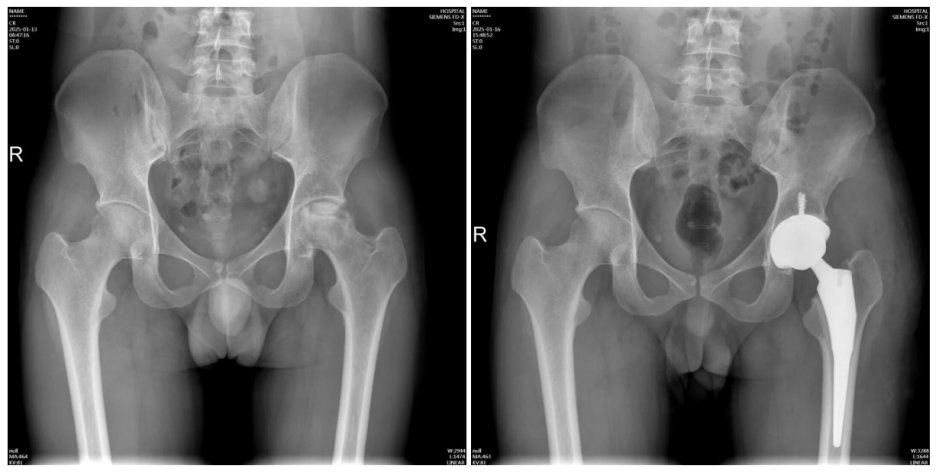

据广东省中医院,该院近日收治了一名30岁的男子,他在两年前出现左髋关节疼痛,最近半年加重了不少。检查发现,他的左侧股骨头缺血性坏死,已经到了晚期,发生了塌陷、变形。由于保守治疗症状没好转,只能进行髋关节置换手术。

患者术前术后X光片对比。图自广东省中医院

髋关节是我们人体最大的承重关节,严重的股骨头坏死,不仅会出现髋关节的疼痛,而且不能下蹲、不能行走,很影响正常生活。